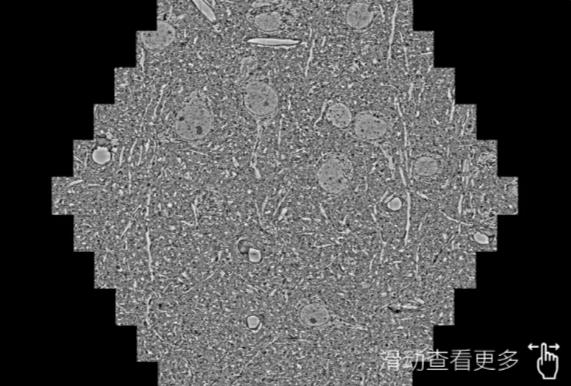

鼠脑切片。左图使用黔南蔡司黔南扫描电镜MultiSEM706对165μmx143pm面积区域成像,耗时仅需1.5秒。右图为鼠脑切片中30μm区域放大效果。样品由芝加哥大学B.Kasthuri提供。

使用蔡司高速黔南扫描电镜MultiSEM对1mm²人脑皮层组织进行高分辨成像,并对其中的各种细胞结构进行三维重构分析。左图展示了2x3mm²组织平面中锥体神经元的三维重构效果。右图显示了局部体积神经元三维重构。图像由哈佛大学chtman实验室提供,渲染图由D. Berger 制作。